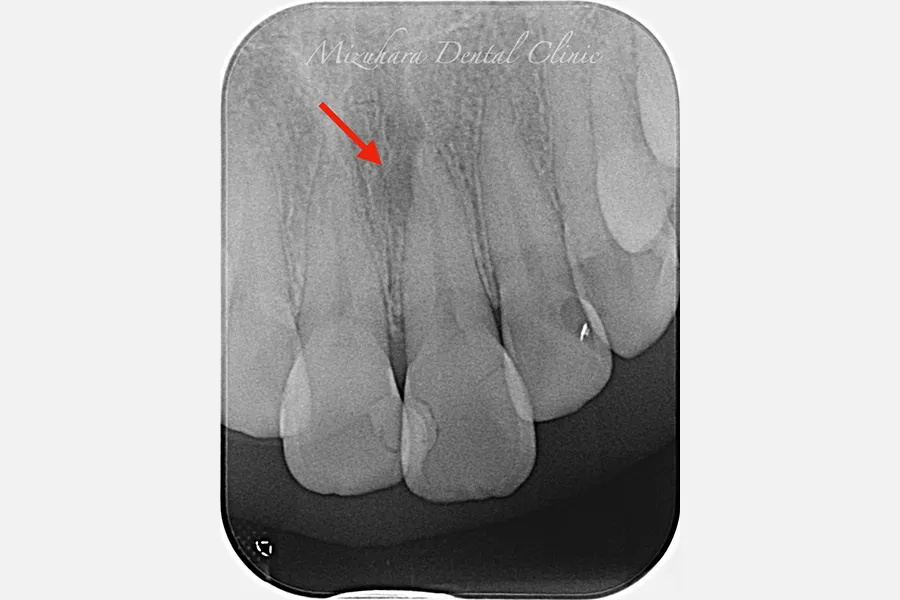

予知性の高い治療を提供できるだけ患者様の大切な歯を残し、10年、20年先まで健康な状態を保てるよう、長期的な視点で治療を計画します。そのために最も重要なのが、「診査」と「診断」です。的確な診断は精密な診査から生まれ、治療結果を大きく左右します。問診や簡易検査だけでは見逃されがちな病変も、CTやマイクロスコープなどの最新の医療機器を活用し、時間をかけて丁寧に「診査・診断」を行います。

世界基準の成功率を目指した精密根管治療

当院では豊マイクロスコープ、ラバーダムを使用し、世界基準の成功率を目指した精密根管治療による「歯を残す」ための治療をご提供します。